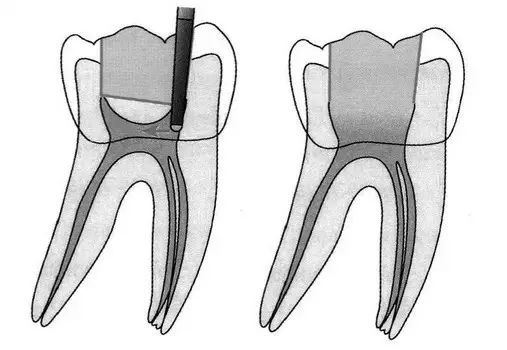

“G型扩孔钻预备:应用GG钻预备根管冠2/3可获得良好的根管冠部通道。GG钻进人根管前,一定要用10#或l5#根管锉探查和通畅根管,如果GG钻1#进入根管有困难时,应初步预备根管,再使用GG钻进入。一般来说,GGl#进入根管l6~17mm;GG2#,GG3#后退2~3mm;GG4#进入根管口下2~3mm;GG5#,GG6#仅作根管口以上部分预备,便于髓腔与根管口形成直线通道。GG钻勿进入根管的深部,避免过度去除牙本质,造成根管壁的薄弱,形成穿孔或瓶颈样预备(见下图)”

口腔H锉怎么消毒牙科医生必须看看----经典根管治疗总结_https://www.jmylbn.com_新闻资讯_第26张

图 根管带状侧穿(stripping,lateral wall perforation)

口腔H锉怎么消毒牙科医生必须看看----经典根管治疗总结_https://www.jmylbn.com_新闻资讯_第27张

图 根管的瓶颈样预备(右图)